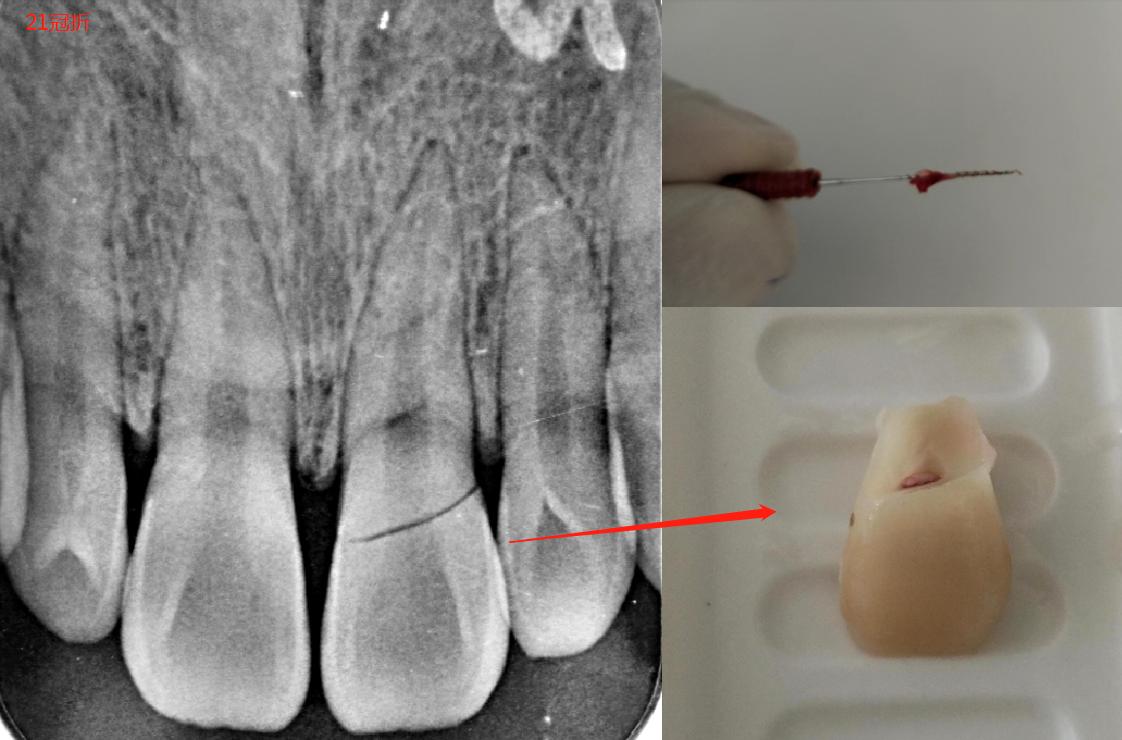

做完根管治疗后,后期修复根据牙齿缺损大小来选择如何修复,一般死髓牙,牙齿缺损大的(比如真牙只剩牙根了),建议打桩行冠修复。

以上几条,都是建立在牙根没有问题的前提下写的,如果牙根断了。。。。。

大概率需要拔除患牙了,小概率的事儿(根尖手术,根管倒充填,根管水泥,正畸牵引牙根)就不谈了。。。。